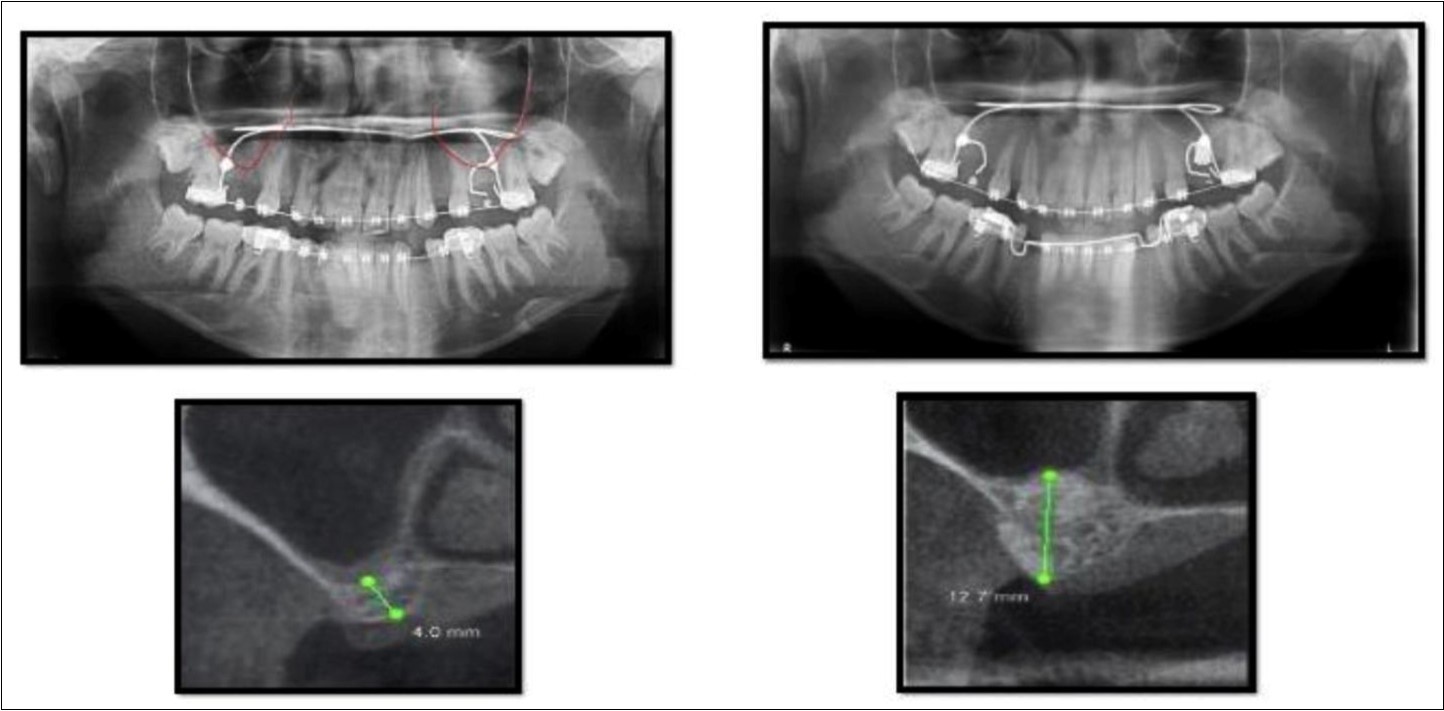

A 19 year old young woman was referred to Department seeking options for rehabilitation of missing right upper first molar with fixed prosthesis as she was uncomfortable with the removable partial denture in relation to 16. The residual bone height in region was 4 mm in 16 tooth region. Patient was taken-up for direct sinus elevation via lateral window approach for sinus augmentation in relation to 16. Under aseptic conditions and local anesthesia, lateral wall of maxilla was exposed after muco-periosteal flap elevation. A window was created of 1cm diameter corresponding to apical aspect of 16. Sinus membrane was identified and elevated using sinus elevators and reamers without perforating the lining. Once the sinus membrane was elevated, graft material was dispensed to achieve an augmentation of 1cm assessed clinically and confirmed using post-operative OPG. At the end of 6 months, a CBCT scan showed an increased bone height of 12.7 mm. (Figure 6)

Figure 6.Pre-operative and post-operative Orthopantomographs and cross sections of CBCT showing residual alveolar bone height